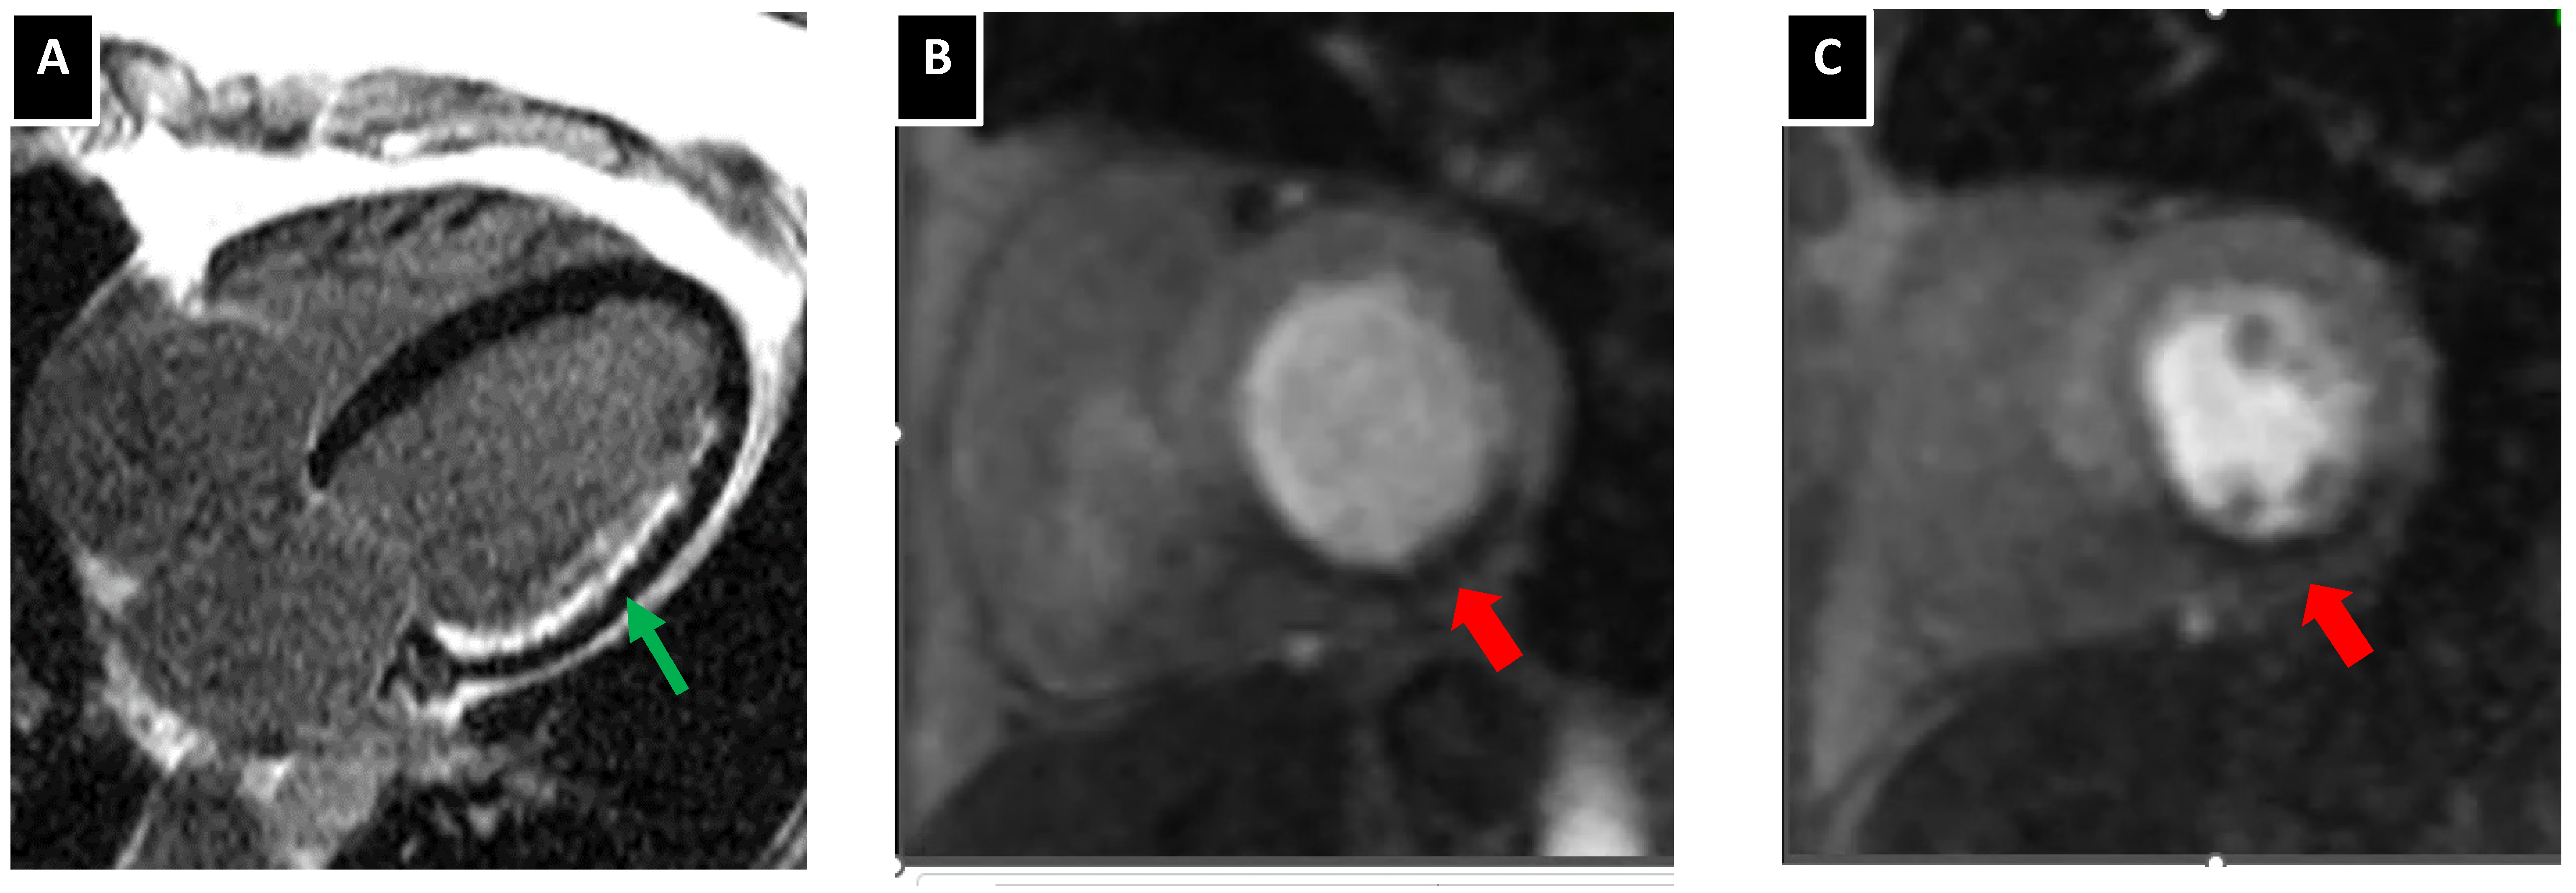

5.3. Atherosclerotic Plaque Characterization with Cardiac MRI